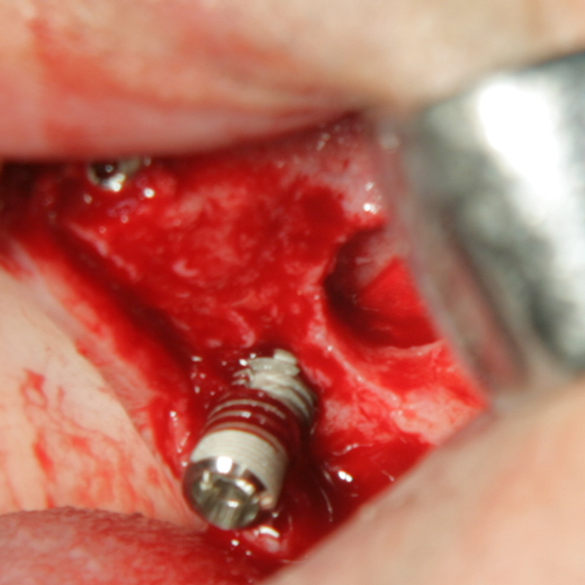

Отворен максиларен синус в началото на интервенцията. Случаят е интересен със следното - твърде атипична форма на трепанационния отвор. На какво се дължи на това - на лошо планиране на оперативния достъп или на нещо друго? Дължи се на факта, че отначало въпросната намеса беше планирана като балонен синуслифт; за съжаление обаче мембраната на синуса се разкъса и надуването на балона стана невъзможно.